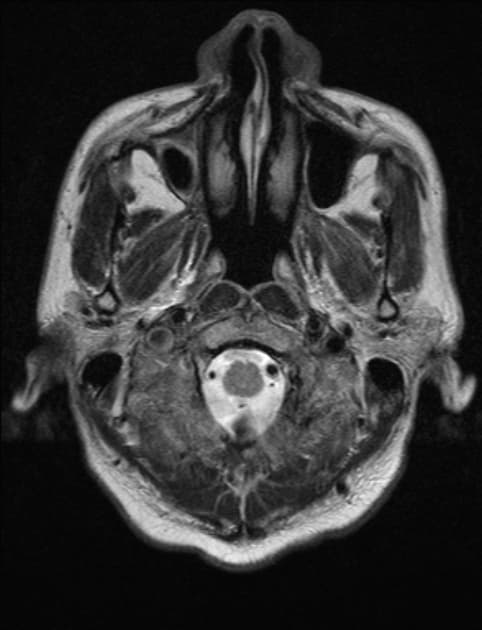

CT

Ở bệnh nhân nghi ngờ nhiễm khuẩn nhu mô não, cần thực hiện chụp CT trước và sau tiêm thuốc cản quang, trừ khi kế hoạch là sẽ tiến hành MRI bất kể kết quả CT. Các hình ảnh điển hình bao gồm:

viền ngoài giảm tỷ trọng và viền trong tăng tỷ trọng (dấu hiệu viền kép – double rim sign) trong hầu hết các trường hợp

vòng mô đồng tỷ trọng hoặc tăng tỷ trọng, thường có độ dày đồng đều

trung tâm giảm hấp thụ tia (dịch/mủ)

vùng xung quanh giảm tỷ trọng (phù vận mạch)

viêm màng não thất có thể hiện diện, biểu hiện bằng ngấm thuốc ở lớp biểu mô não thất (ependyma)

giãn não thất do tắc nghẽn thường được thấy khi có lan vào não thất